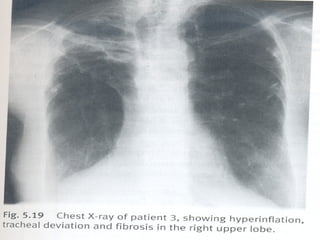

Imagem

Radiografia simples de tórax

- Póstero-anterior

ATELECTASIA

 INSPEÇÃO ESTÁTICA - RETRAÇÃO

 INSPEÇÃO DINÂMICA – DIMINUIÇÃO DA

EXPANSÃO E TIRAGEM

 PALPAÇÃO – EXPANSIBILIDADE

DIMINUIDA OU ABOLID, FTV – ABOLIDO

 PERCUSSÃO – MACICEZ ( NAS

CRÔNICAS )

 SUBMACICEZ ( NAS

AGUDAS )

 AUSCULTA- MV ABOLIDO, BRONCOFONIA

DIMINUIDA